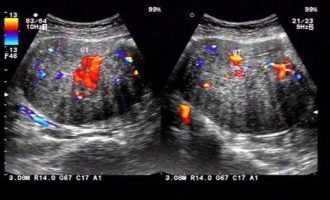

- B超檢查:若HCG達(dá)到一定水平(通常>2000 IU/L)但宮內(nèi)未見孕囊,需高度懷疑生化妊娠或?qū)m外孕。